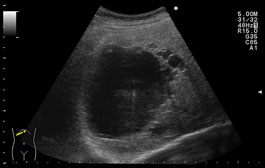

肝臓所見 〜肝嚢胞〜

今日は、腹部エコーで発見される肝臓の所見のなかで最も多い肝嚢胞についてお話ししようと思います。

肝嚢胞は、液体が貯留した袋状のものです。単発、あるいは多発し、通常は無症状ですが、

大きくなると腹部膨満感、圧迫感を感じる方もいらっしゃいます。

定期的な腹部エコー検査により大きさの変化や腫瘍の可能性がなく、無症状であれば

経過観察でよいとされています!